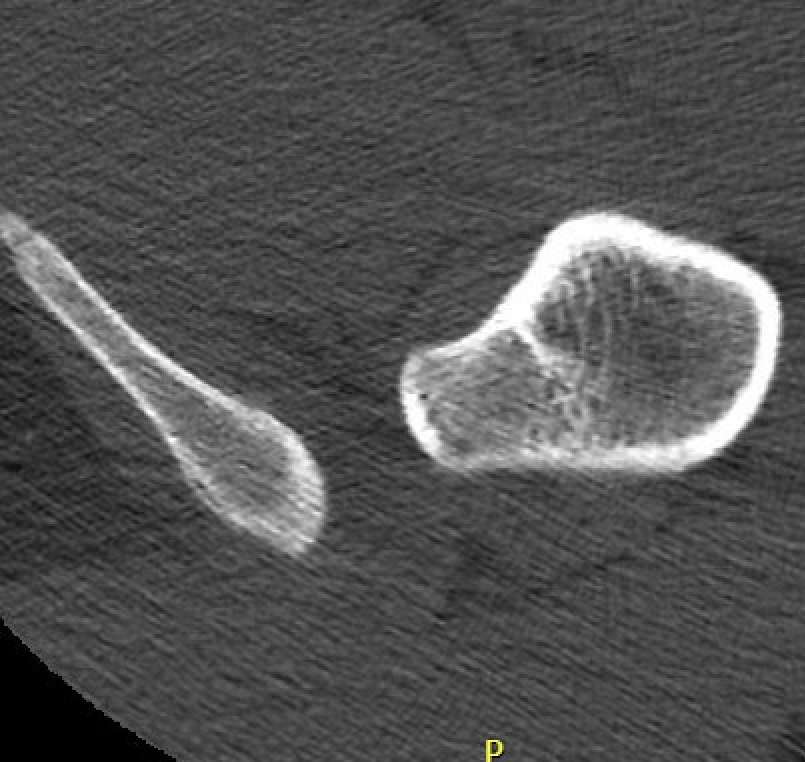

Definition

Narrowing of the ischiofemoral space between lateral ischium and lesser trochanter

Entrapment / compression of quadratus femoris

- enlarged lesser trochanters

- osteochondromas

Reduced ischiofemoral space - distance between the lesser trochanter and the ischial tuberosity

CT